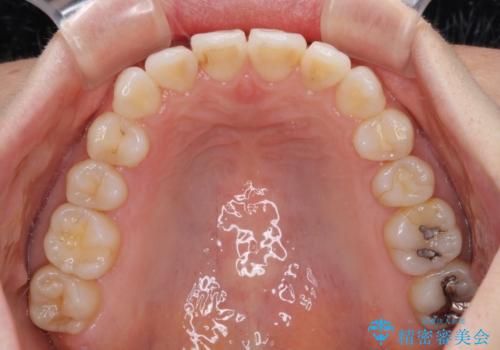

- ワイヤーではない矯正治療があると聞いたとのことで来院された患者様です。

長年前歯のデコボコを気にしていたもののワイヤー矯正に抵抗があり躊躇していたそうですが、インビザラインなら治療してみたいとのことで相談にいらっしゃいました。

インビザライン適用の歯列であったため、歯と歯の間を削るIPRを用いて改善することとしました。